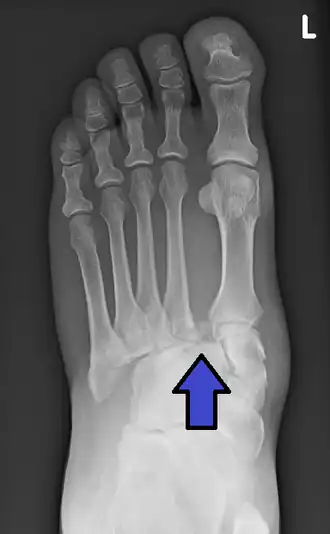

Lors d'une blessure traumatique à haute vélocité au milieu du pied, le diagnostic d'une entorse de Lisfranc doit être évoqué. Face à une telle blessure, la suspicion clinique doit être élevée. Dans certains cas, on peut noter à l'examen physique une plaie sus-jacente et une compromission de l'apport sanguin au pied distal. On note une déformation du milieu du pied et des anomalies évidentes à la radiographie. La trouvaille radiographique classique est un espace entre la base des premier et deuxième orteils[9].

Le diagnostic est plus difficile dans le cas de traumatismes à faible énergie, notamment dans les sports. À l'histoire, le patient peut se présenter seulement avec un inconfort à la mise en charge et un léger gonflement de l'avant-pied ou du milieu du pied. Des ecchymoses de la voûte plantaire ont été décrites comme diagnostiques dans ces circonstances mais pourraient bien être absentes[10]. En règle générale, la radiographie conventionnelle du pied est utilisée avec des vues standard sans mise en charge, complétées par des vues avec mise en charge, qui peuvent démontrer un élargissement de l'intervalle entre les bases du premier et deuxième orteils lorsque les vues initiales ne montrent pas d'anomalie. Les radiographies dans de telles circonstances ont une sensibilité de 50% sans mise en charge et de 85% avec mise en charge[11].